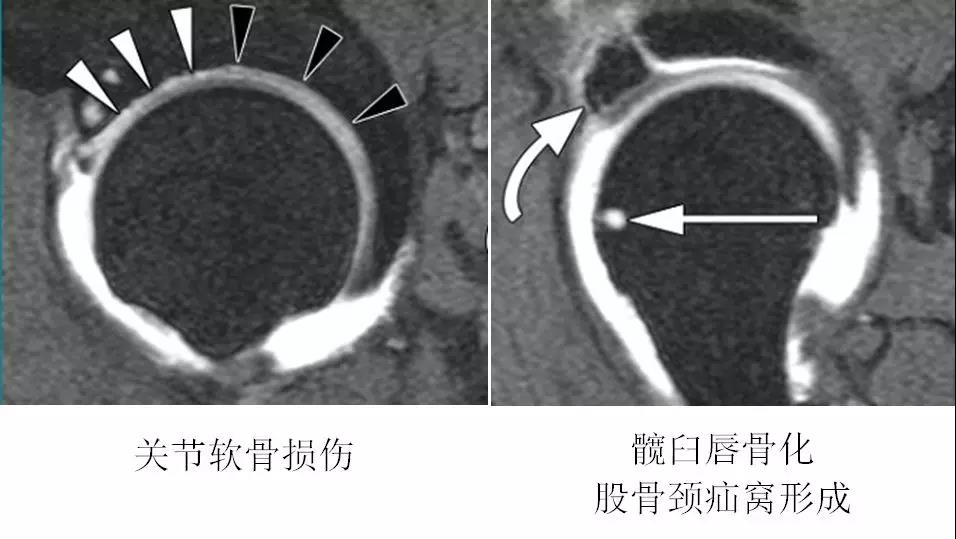

CT表现

- CT表现与X线平片相同。

- 能更清晰显示细微骨质结构改变:髋臼边缘的骨赘、股骨颈疝窝、关节面下囊变等细节。

钳夹撞击型FAI▼

- 横断面显示髋臼后倾:正常髋臼连线与水平线呈钝角;呈锐角,提示髋臼后倾。